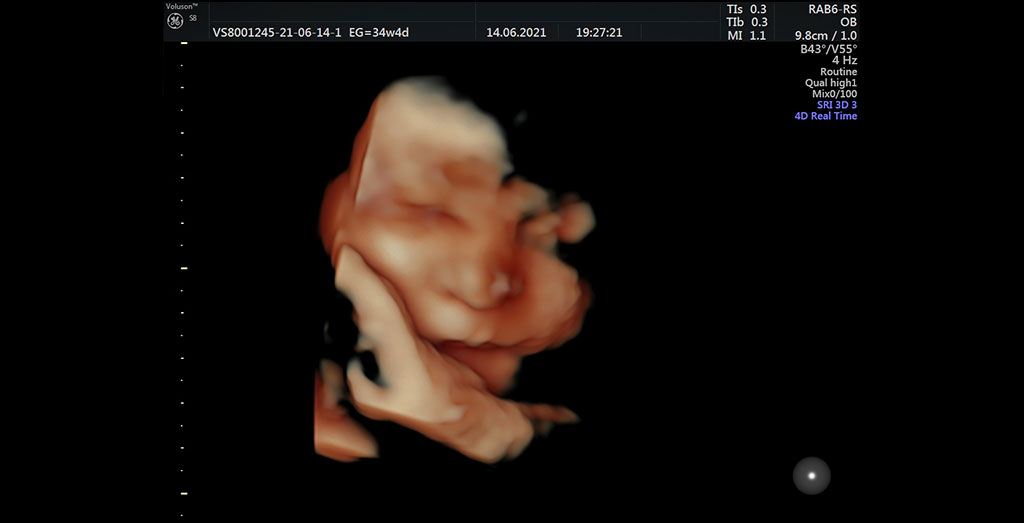

Ecografía 4D

La Ecografía en 4D permite obtener imágenes en movimiento y vídeos en tiempo real del bebé con una calidad superior a la ecografía 3D, permitiendo ver los movimientos fetales en directo.